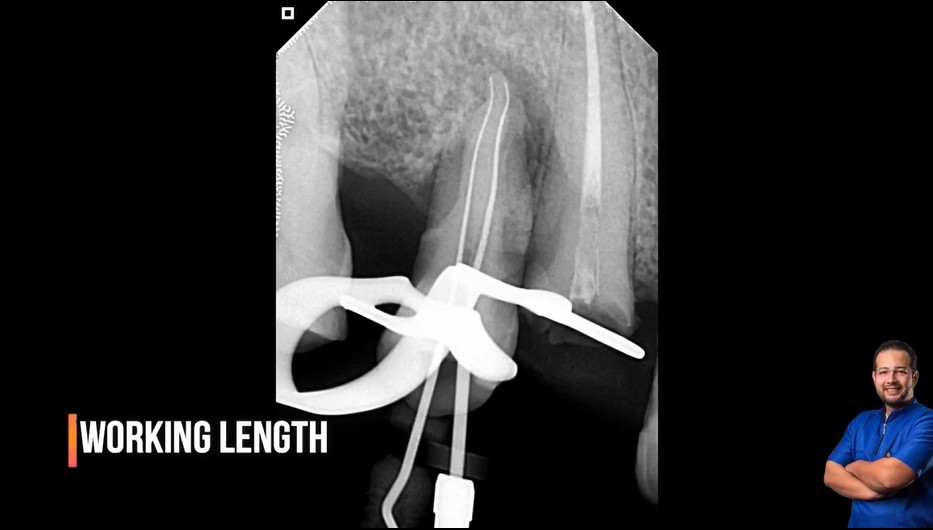

Treatment case sharing from dr wael